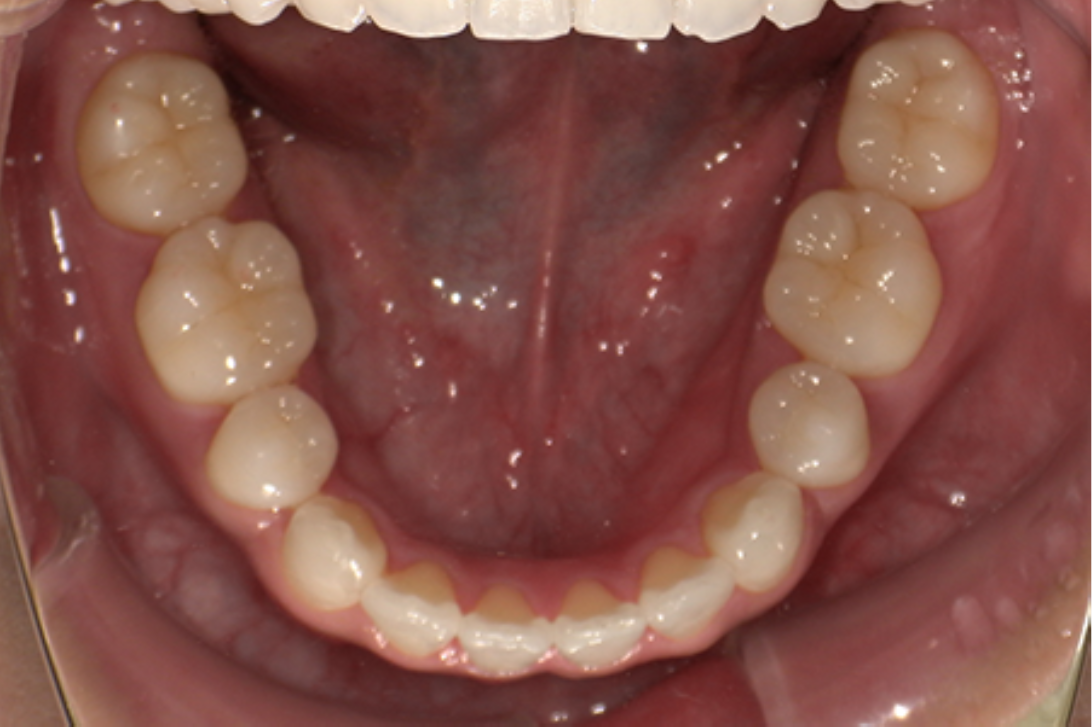

主訴:前歯が出ている

診断:叢生、上顎前突

治療内容:唇側矯正治療

年齢:22歳

治療に用いた装置:マルチブラケット装置

抜歯or非抜歯:抜歯(上下顎両側小臼歯)

期間:20ヶ月

回数:20回

費用:990,000円(税込)

リスク・副作用:虫歯、歯肉炎、歯肉退縮、歯根吸収、後戻りなど